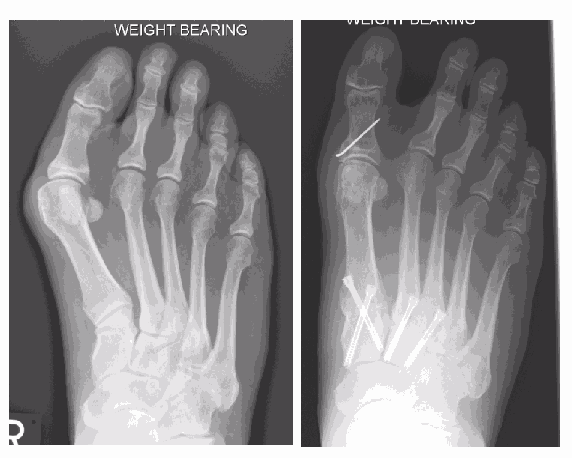

This X-ray shows a significant bunion (hallux valgus) only. The first metatarsal (a) in isolation has drifted away from the second (b)

This X-ray shows a bunion, however the metatarsus adductus angle is significant, reflecting the medial drift of the first three metatarsals towards the inside of the foot. Now the bunion cannot be corrected by just addressing the first metatarsal alone.

The far X-ray shows the bunion and metatarsus adductus angles having been successfully addressed by fusion the medial three metatarsals with screw fixation.